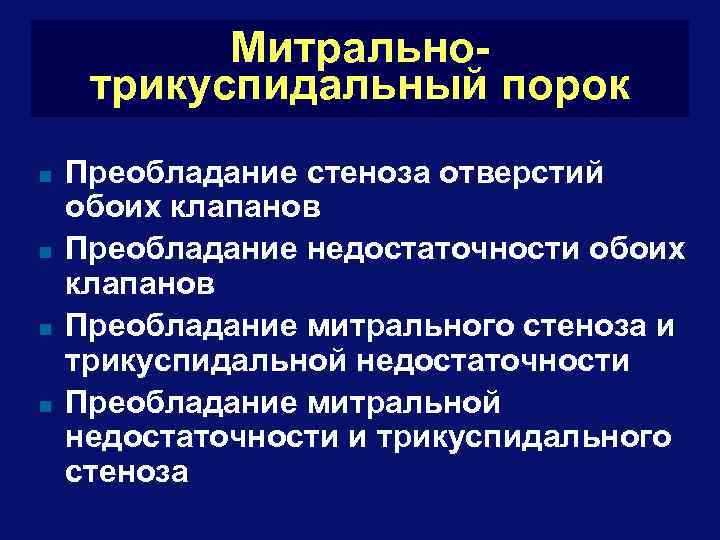

Митральнотрикуспидальный порок n n Преобладание стеноза отверстий обоих клапанов Преобладание недостаточности обоих клапанов Преобладание митрального стеноза и трикуспидальной недостаточности Преобладание митральной недостаточности и трикуспидального стеноза